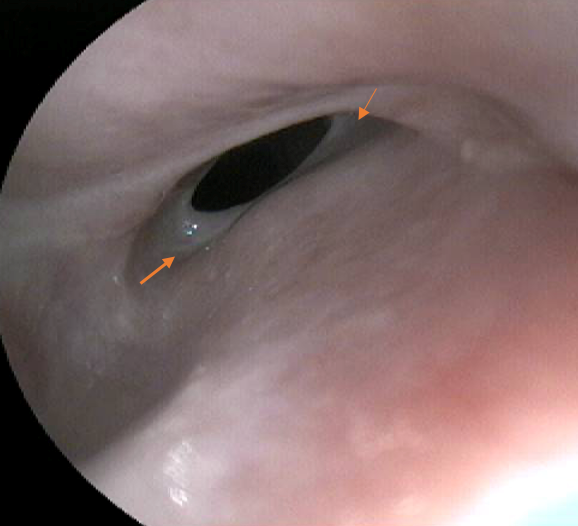

However, ten days post-removal, the dog began regurgitating food shortly after eating and a subsequent endoscopy was performed to localise and visualise the meatus of the oesophageal stricture. A fibrous ring was visible but there was no evidence of significant oesophageal ulceration.

Endoscopic appearance of oesophageal stricture